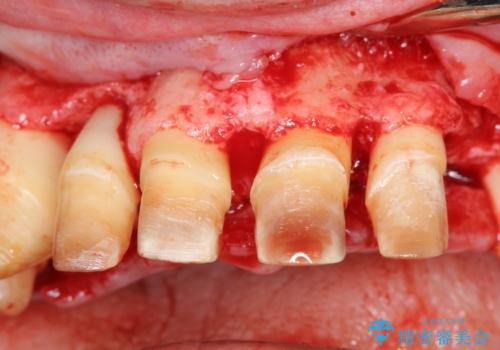

エムドゲインを用いた歯周病再生治療

奥歯は重度歯周病で残せない状態でしたが、前歯にも歯周病により歯の周囲の骨が溶けてしまい中等度の歯周病が見られました。

エムドゲインを用いて溶けてしまった歯の周囲の再生を計画します。

今回治療前は歯周ポケットの値は7mmと、中〜高度の歯周病の状態でしたが、エムドゲインを用いた歯周病再生治療を行うことで、歯周ポケットは3mmまで回復し出血もなく良好な状態を維持しています。